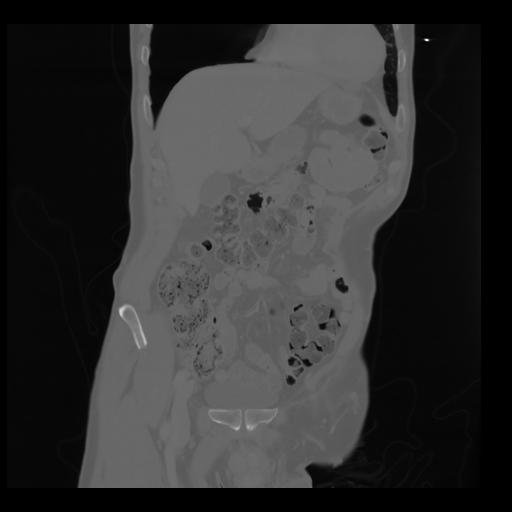

35 CUERPO,CE,Coronal,3.000,CUERPO,Coronal,